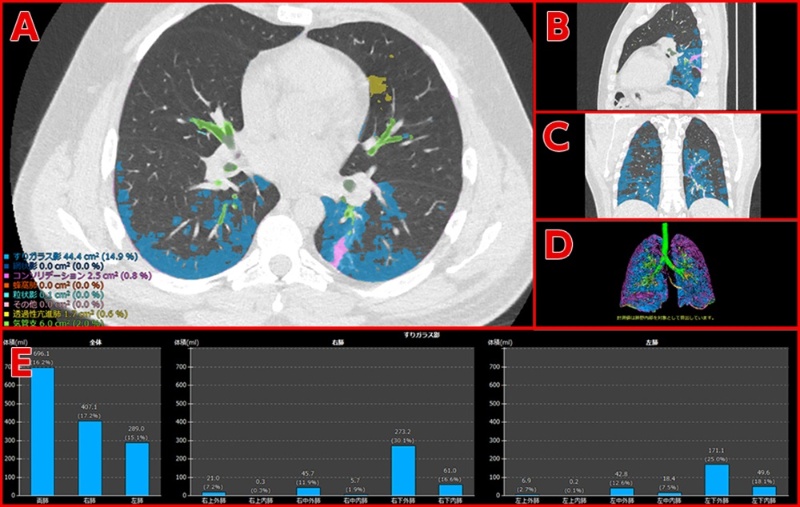

Aiで新型コロナ患者の治療効果の判定を支援 富士フイルム 日経クロステック Xtech